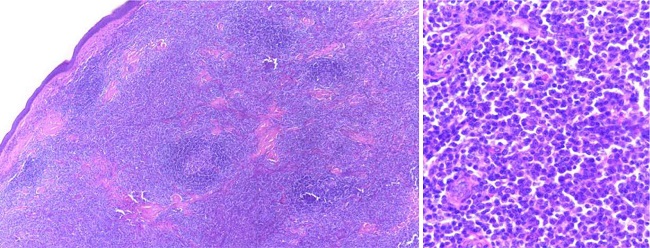

Ao exame, apresentava pápulas e nódulos túmidos agrupados, formando uma placa de 1,5 x 1,2cm no braço esquerdo. Não apresentava linfonodomegalias periféricas ou visceromegalias palpáveis. As hipóteses clínicas incluíam linfoma cutâneo, sarcoidose, pseudolinfoma, lúpus túmido e sífilis terciária. Ao exame histopatológico com ensaio imuno-histoquímico, apresentava infiltração linfocitária nodular e difusa na derme, com 60% deste infiltrado composto por linfócitos (CD20+, CD10- e BCL6-), frequentes linfócitos T reacionais (CD3+), índice de proliferação pelo Ki67 relativamente baixo (10-20%), frequentes plasmócitos e restrição de cadeias leves de imunoglobulina (índice kappa: lambda maior que 10:1), sugerindo o diagnóstico de linfoma B da zona marginal (Figuras 2 e 3).